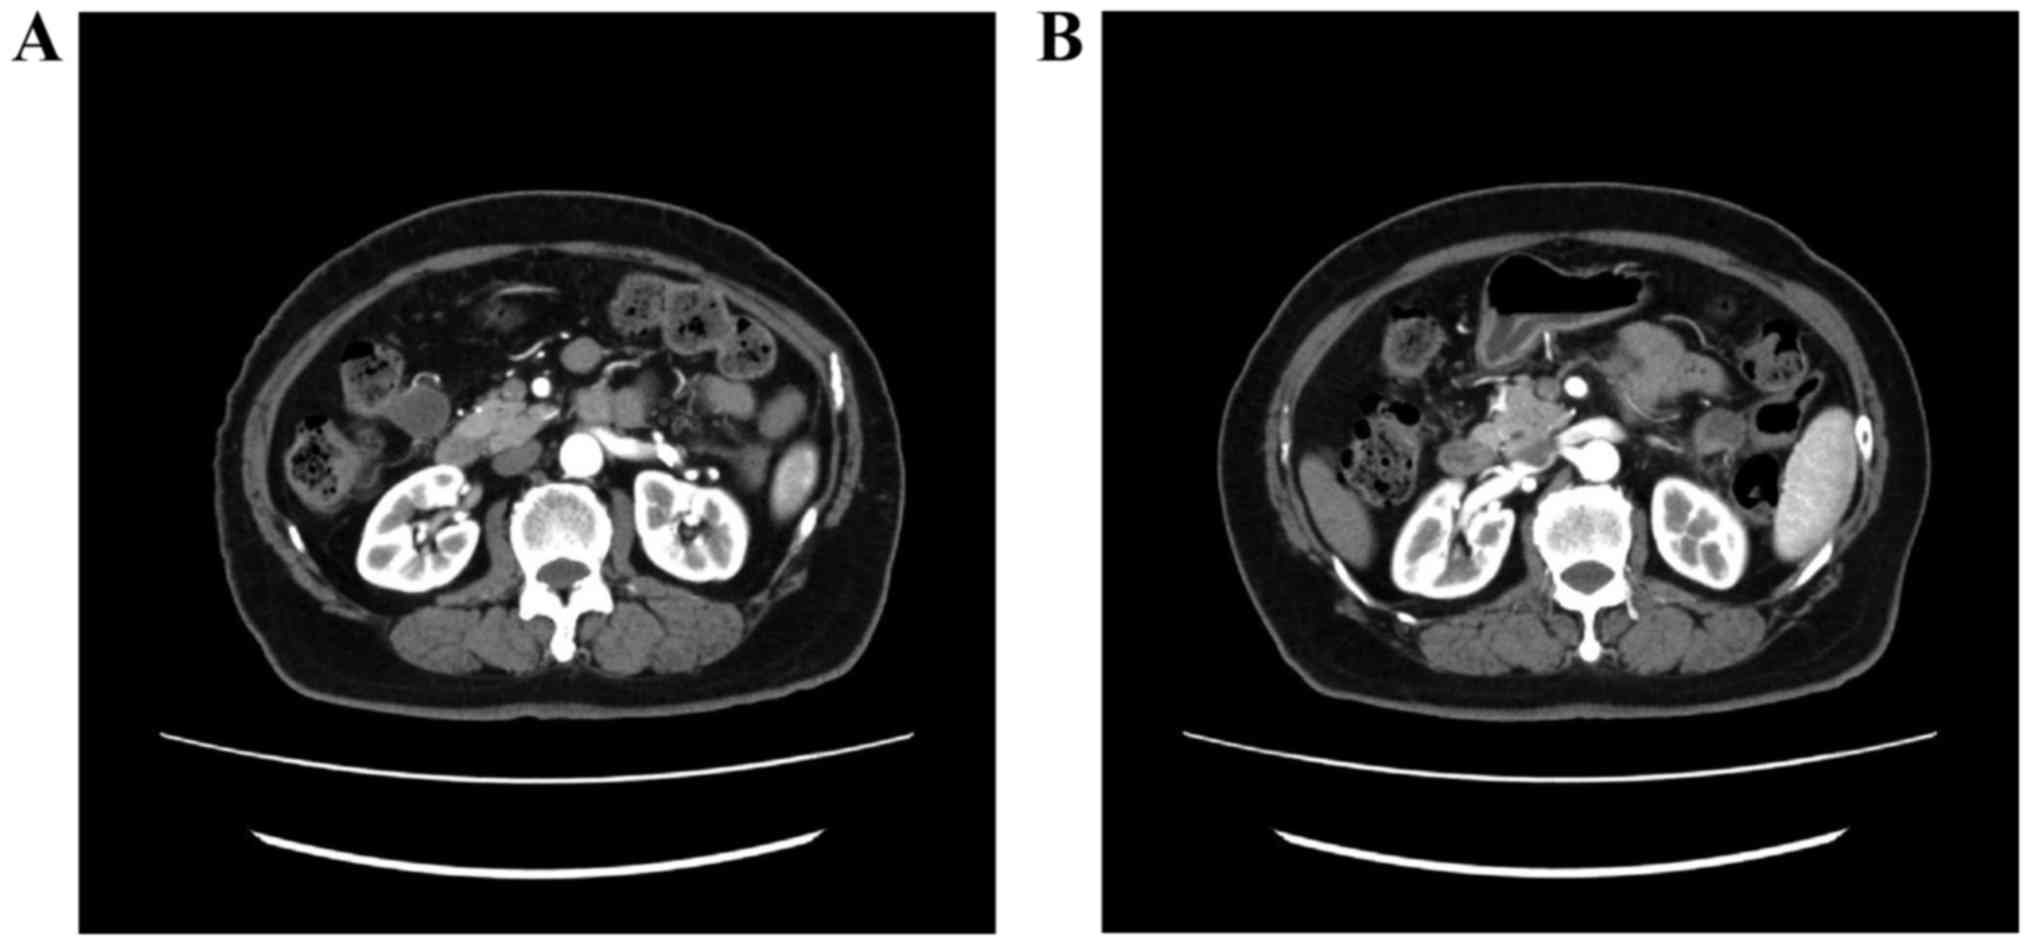

A 79-year-old woman, gravida 1, para 0, presented with lower abdominal pain. The patient was examined in a gynecological clinic (September, 2012). Magnetic resonance imaging (MRI) revealed a mass sized ~4 cm in the endometrium (Fig. 1) and computed tomography (CT) revealed two 2-cm peritoneal disseminations (Fig. 2). The carbohydrate antigen-125 level was 53 ng/ml (normal range, <35 ng/ml), and the carcinoembryonic antigen level was 8.6 ng/ml (normal range, <5.0 ng/ml). The diagnosis was endometrial adenocarcinoma. The patient had a history of type 2 DM and hypertension, but was not obese (body mass index, 23.6 kg/m2). The HbA1c level (National Glycohemoglobin Standardization Program) was 9.1%, and the patient was treated with oral medications [sulfonylurea and dipeptidyl peptidase-4 (DPP-4) inhibitor].

Figure 2.

Computed tomographic images showing peritoneal dissemination. (A) Dorsal side of the transverse colon and (B) anterior side of the left kidney.